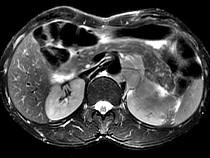

问题 男,54岁、1年前行胃癌切除术,现消瘦乏力、左锁骨上淋巴结肿大,影像检查如图,最可能的诊断是()

选项 A.淋巴瘤 B.腹膜后淋巴结转移 C.肾上腺腺瘤 D.肾上腺增生 E.腹膜后纤维肉瘤

答案 B